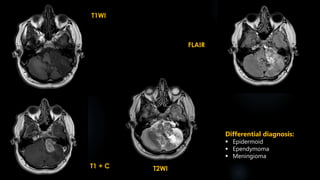

T1 + C

T1WI

DWI T2WI FLAIR

Differential diagnosis:

 Dermoid

 Acoustic neuroma

 Craniopharyngioma

 Arachnoid cyst